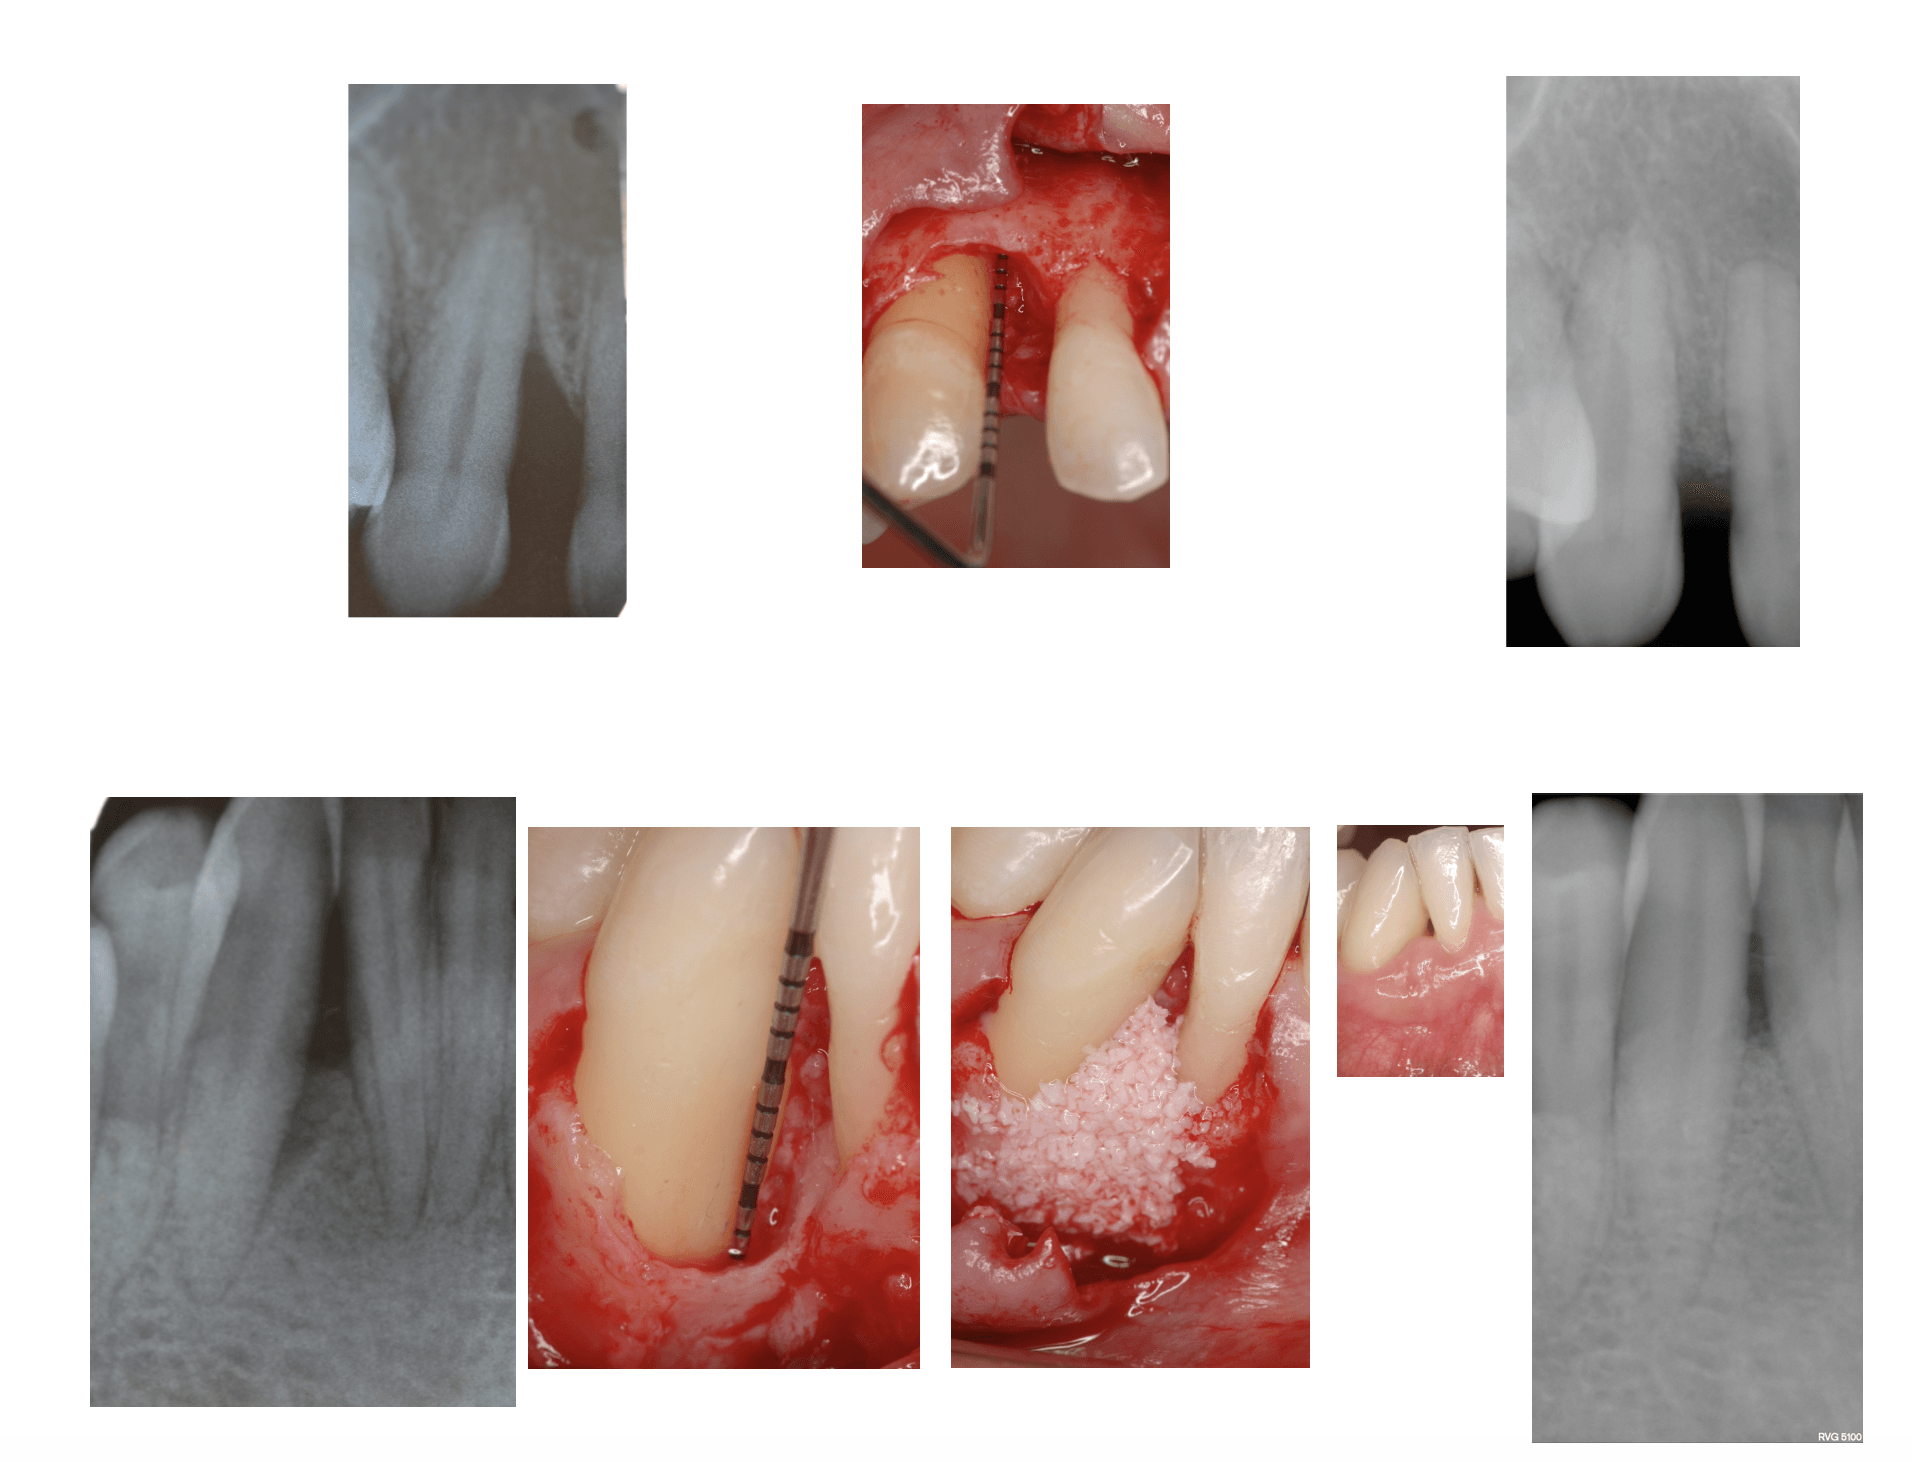

La chirurgia implantare meglio conosciuta come implantologia, può essere definita come un intervento chirurgico atto a riabilitare la funzione masticatoria ed estetica in pazienti affetti da edentulia (mancanza di denti) parziale o totale.

Attraverso le nuove tecniche implantoprotesiche, oggi è possibile sostituire degli elementi dentali mancanti, mediante l’inserimento di manufatti in lega di titanio totalmente biocompatibili ad altissima tecnologia, direttamente all’interno dell’osso, su cui vengono poi istallate una o più protesi fisse, riabilitando da un singolo elemento dentale fino ad un’intera arcata, con risultati tali da soddisfare il paziente sia da un punto di vista estetico che funzionale. Possono distinguersi due tipi d’intervento:

l’implantologia a carico differito e l’implantologia a carico immediato. Il primo è caratterizzato dall’inserimento della protesi solo ad osteointegrazione avvenuta, presupponendo un’attesa che varia dai tre ai sei mesi; il secondo invece dalla possibilità di inserire una o più protesi entro 24-72 ore dall’intervento.

Questa patologia rappresenta una delle cause della perdita di tessuto connettivo, del riassorbimento dell’osso alveolare e della formazione di tasche parodontali che possono condurre alla perdita dei denti ed è una delle cause più comuni della perdita dei denti negli adulti. Grazie alla chirurgia orale per queste tipologie di malattie infiammatorie che colpiscono il tessuto di sostegno del dente, vengono eseguiti dei trattamenti parodontali come il curettage ( ossia il procedimento di rimozione del tartaro o della placca dalla parete orale al di sotto della gengiva) o la levigatura delle radici a cielo aperto, o ancora interventi definiti rigenerativi per l’aumento dello spessore osseo, innesti gengivali, rimozioni di cisti dentali o tumori del cavo orale. Questa tipologia d’intervento consente di ricostruire il tessuto danneggiato o perso e può avvenire in contemporanea all’intervento implantare (rigenerazione ossea perimplantare) o prima di effettuare l’intervento stesso ( rigenerazione ossea preimplantare). La rigenerazione ossea può avvenire in due modi: tramite l’auto trapianto osseo, ossia il prelievo dell’osso da una parte del corpo del paziente e l’innesto nella gengiva, oppure si procede con l’applicazione di osso artificiale, realizzato in materiale sintetico e biocompatibile, che istallato nella gengiva e ricoperto da una membrana riassorbibile, si integra perfettamente con l’osso. Il nostro studio medico dentistico, grazie alla consolidata collaborazione con il dipartimento di parodontologia della facoltà di Odontoiatria dell’Università “La Sapienza “ di Roma e alla comprovata esperienza nel campo implantologico e parodontale è in grado d’intervenire con entrambe le modalità, garantendo al paziente la massima efficienza